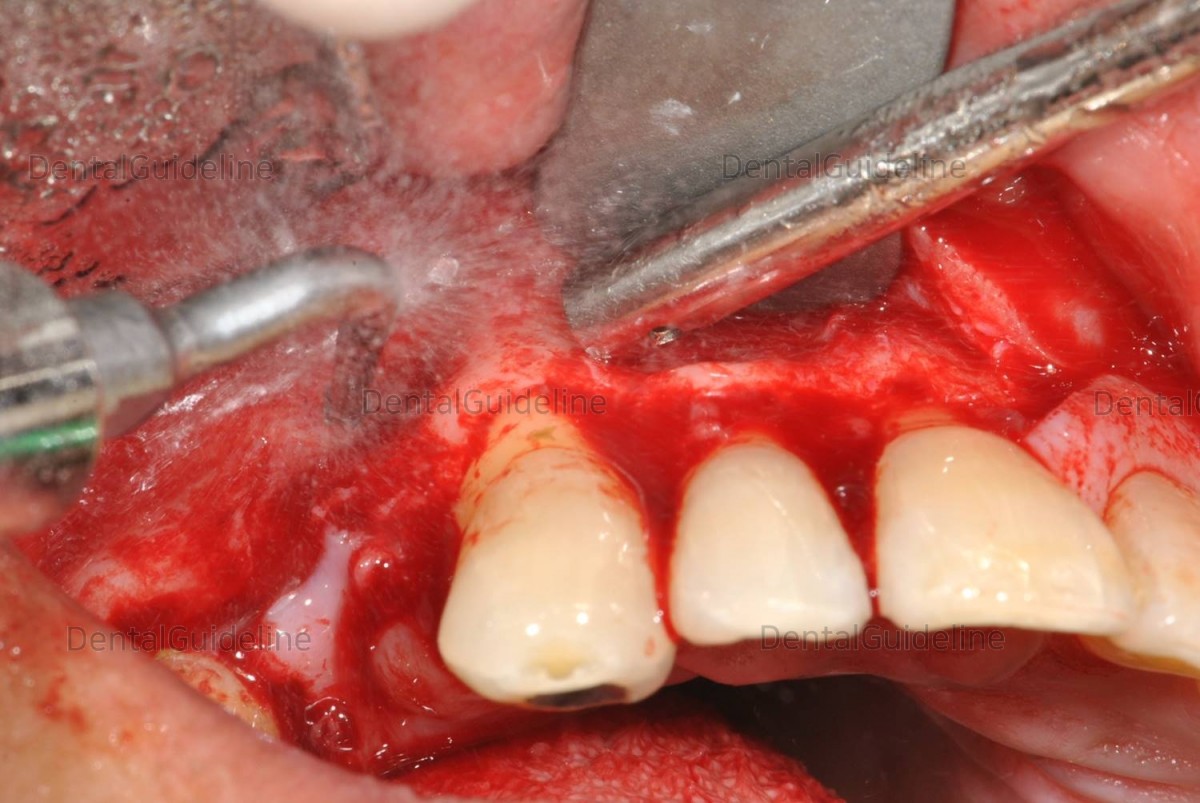

5. Removal of the lateral bone wall of the cyst using the piezo machine.

7. Piezo machine in action.

8. lateral wall of the cyst was removed.